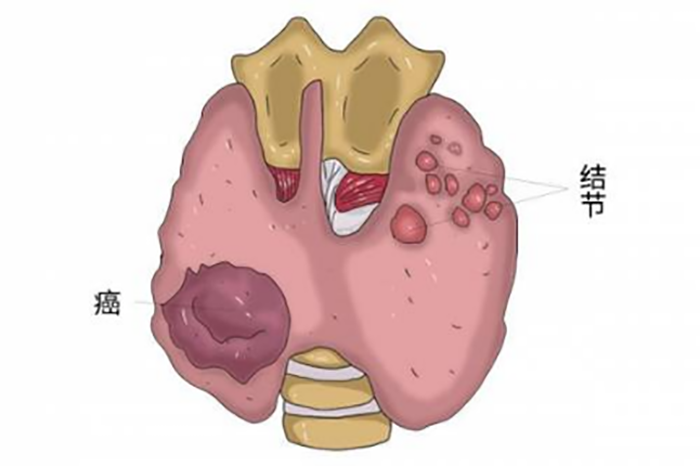

甲状腺是颈部正中偏下的一个蝴蝶状器官,主要功能是分泌甲状腺激素,在人体代谢等方面发挥重要作用。

甲状腺结节是甲状腺细胞的异常生长产生的“肿块”,可能是单个,也可能是多个。

绝大多数情况下,超过90%的甲状腺结节是良性的,只有5%-15%的甲状腺结节为恶性,即甲状腺癌。